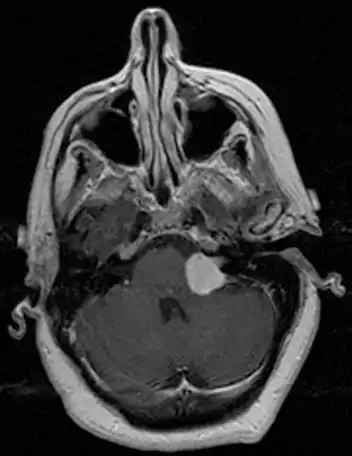

Bilateral schwannomas in a patient with neurofibromatosis 2

For the most part, unilateral sporadic vestibular schwannomas are readily treated successfully by modern medical techniques. Having bilateral VSs is a more troublesome condition. Bilateralism is considered to be the hallmark and main diagnostic criterion of Neurofibromatosis Type II (NF2), a genetic disorder that is heritable, progressive, difficult to manage, and has a 1 in 2 chance of being passed on to each offspring. NF2 patients tend to have a more severe mutation, although there are mild mosaic cases in which only some cells carry the mutation. Genetic testing confirming mutation of the NF2 gene is recommended. About 50% of people with NF2 have a de novo mutation, and about 50% of these new mutations will be mild mosaic cases which are less likely to be passed on. NF2 patients may develop other cranial and spine tumors. NF2 develops during the teens or early adulthood, whereas sporadic VSs are diagnosed mostly in patients between the ages of 40–60 years. Both varieties of VS (sporadic and NF2) are very rare, accounting for only about 8% of all primary brain tumors. The incidence of NF2 is approximately 1 per 60,000 people.[6][7][8]